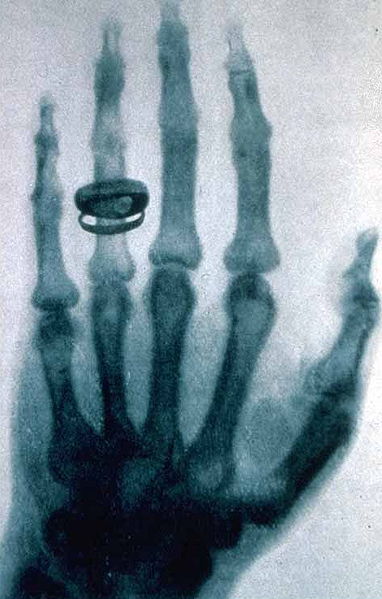

รังสีเอกซ์ (X-ray หรือ Röntgen ray) เป็นรังสีแม่เหล็กไฟฟ้า ที่มีความยาวคลื่นในช่วง 10 ถึง 0.01 นาโนเมตร ตรงกับความถี่ในช่วง 30 ถึง 30,000 พีต้าเฮิตซ์ (1015เฮิตซ์) ในเบื้องต้นมีการใช้ช้รังสีเอกซ์สำหรับถ่ายภาพเพื่อการวินิจฉัยโรค และงานผลึกศาสตร์ (crystallography) รังสีเอกซ์เป็นการแผ่รังสีแบบแตกตัวเป็นไอออน และมีอันตรายต่อมนุษย์ รังสีเอกซ์ค้นพบโดยวิลเฮล์ม คอนราด เรินต์เกน เมื่อ ค.ศ. 1895

ในวันที่ 8 พฤศจิกายน 1896 Wilhelm Conrad R?ntgen นักฟิสิกส์ชาวเยอรมัน ได้เริ่มทำการศึกษาและวิจัยรังสีเอกซ์ขณะทำการทดลองกับท่อสุญญากาศ แล้วในวันที่ 28 ธันวาคม 1895 เขาได้เขียนรายงานเรื่อง On a new kind of ray: A preliminary communication ซึ่งรายงานเล่มนี้ได้พูดถึง รังสี x ซึ่งได้ระบุไว้ว่าเป็นรังสีที่ยังระบุประเภทไม่ได้ (จึงตั้งชื่อไว้ก่อนว่า รังสี x) ส่งผลให้ชื่อรังสีเอกซ์ถูกใช้กันมานิยมมากกว่าชื่อที่นักวิทยาศาสตร์ตั้งให้ว่า รังสีเรินต์เก้น (R?ntgen rays) และทำให้ R?ntgen ได้รับรางวัลโนเบลสาขาฟิสิกส์จากการค้นพบและพิสูจน์ปรากฏการณ์นี้

ในการทดลองของ R?ntgen ได้เริ่มจากการใช้เครื่องสร้างรังสีแคโทดผ่านท่อแก้วสุญญากาศ เขาได้พบว่ามีแสงสีเขียวอ่อนวิ่งปะทะกับผนังท่อ เขาได้พบว่า แสงจากเครื่องสร้างรังสีแคโทดนี้ได้ทะลุผ่านวัสดุต่าง ๆ (เช่น กระดาษ ไม้ หนังสือ) เขาได้เริ่มวางวัตถุอื่น ๆ หลายประเภทไว้หน้าเครื่องนี้ และทำให้เขาได้พบว่า เขาสามารถถ่ายเห็นโครงร่างของกระดูกมือของเขาได้บนผนัง สองเดือนต่อมาเขาเริ่มทำการค้นคว้า และได้ทำการพิสูจน์และตีพิมพ์ในปี 1896 ในรายงานชื่อ On a New Kind of Radiation

ตั้งแต่การค้นพบของ Roentgen ว่ารังสีเอกซ์สามารถบอกรูปร่างของกระดูกได้ รังสีเอกซ์ได้ถูกพัฒนาเพื่อนำมาใช้ในการถ่ายภาพในการแพทย์ นำไปสู่สาขาที่เรียกว่า รังสีวิทยา โดยนักรังสีวิทยาได้ใช้ ภาพถ่าย (radiography) ที่ได้มาใช้ในการช่วยการวินิจฉัยโรคนั่นเอง